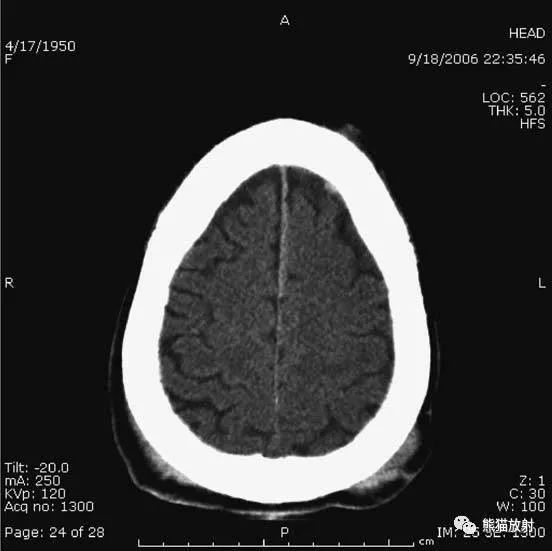

6、脑梗死

缺血性脑卒中早期:脑水肿,灰白质分界模糊,脑沟消失;

中期:病变区域密度减低;

晚期:脑实质体积缩小。

A:陈旧性脑梗死,右枕叶体积缩小;

B:左枕叶急性脑梗死,灰白质分界模糊,脑沟消失;

另一患者:

C、D:亚急性期脑梗死,低密度,无明显占位效应。

▲左侧大脑中动脉供血区脑梗死(亚急性期):

低密度,轻度水肿。

缺血性脑卒中发作2-4天时,占位效应最明显。